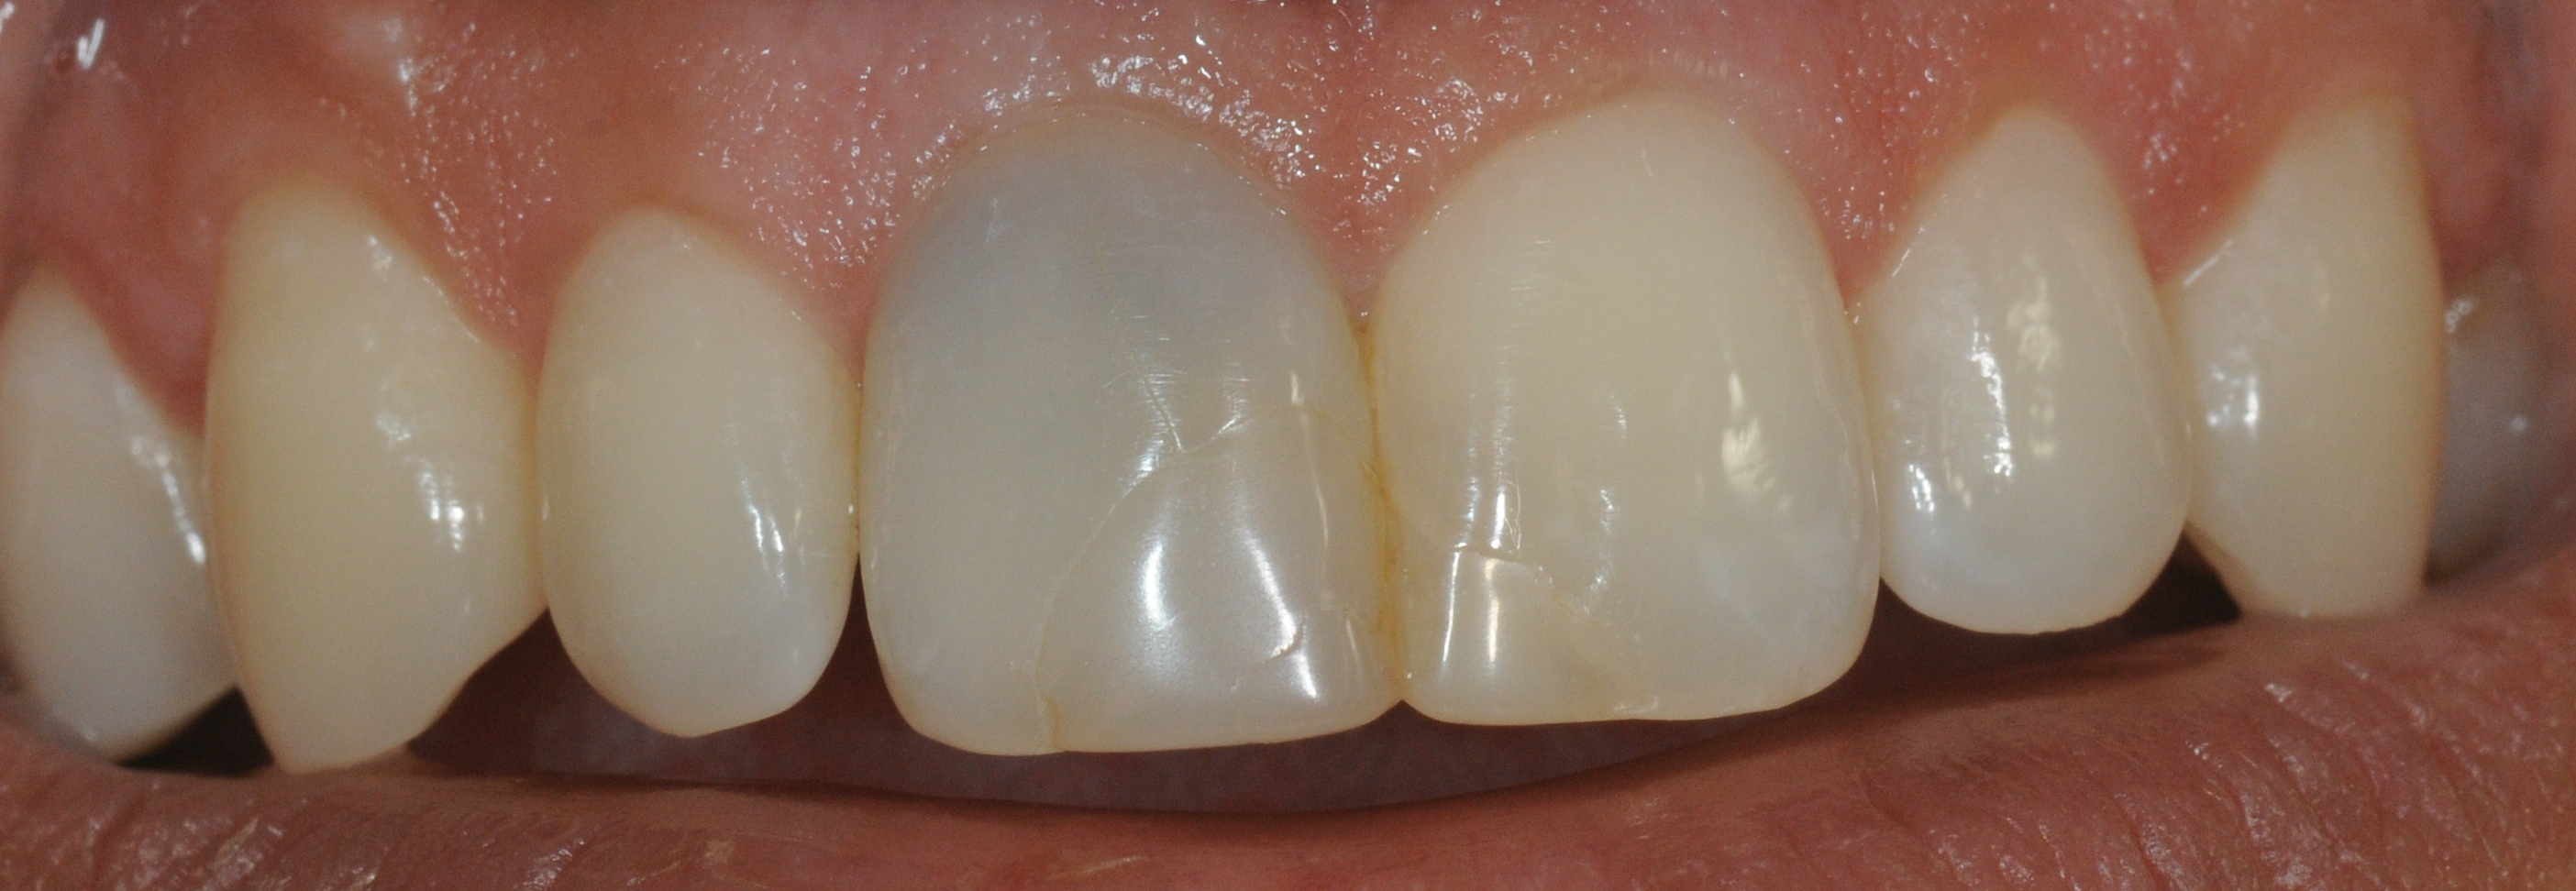

Wurzelbehandelte Zähne können dunkel werden, weil sich Farbstoffe im Zahn einlagern.

Zustand nach einer Woche Bleicheinlage. Der Zahn kann nun mit einer definitiven Füllung versorgt werden.

Es wird auch oft gefragt, wie lange denn der Bleicheffekt anhält. Beim Bleichen werden Farbstoffe, die sich in den Zahn eingelagert haben optisch inaktiviert. Danach sollten eigentlich keine weiteren Farbstoffe mehr da sein, somit sollte das Bleichergebnis dauerhaft sein. Wir haben mittlerweile Langzeitergebnisse von über 17 Jahren. Das Ergebnis hat sich nicht verändert.

Hier ist aber auch deutlich zu sehen, was Internes Bleichen (Bleaching) nicht kann: vorhandene Füllungen bleiben wie sie sind und kommen durchs Bleichen stärker zur Geltung. Diese müssen dann gegebenenfalls getauscht werden, um die Farbe an den gebleichten Zahn anzupassen. Das gleiche gilt für Verfärbungen als Auflagerungen auf dem Zahn, diese werden im Rahmen der Zahnreinigung wegpoliert.